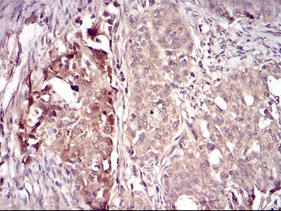

IHC    1/200 - 1/1000